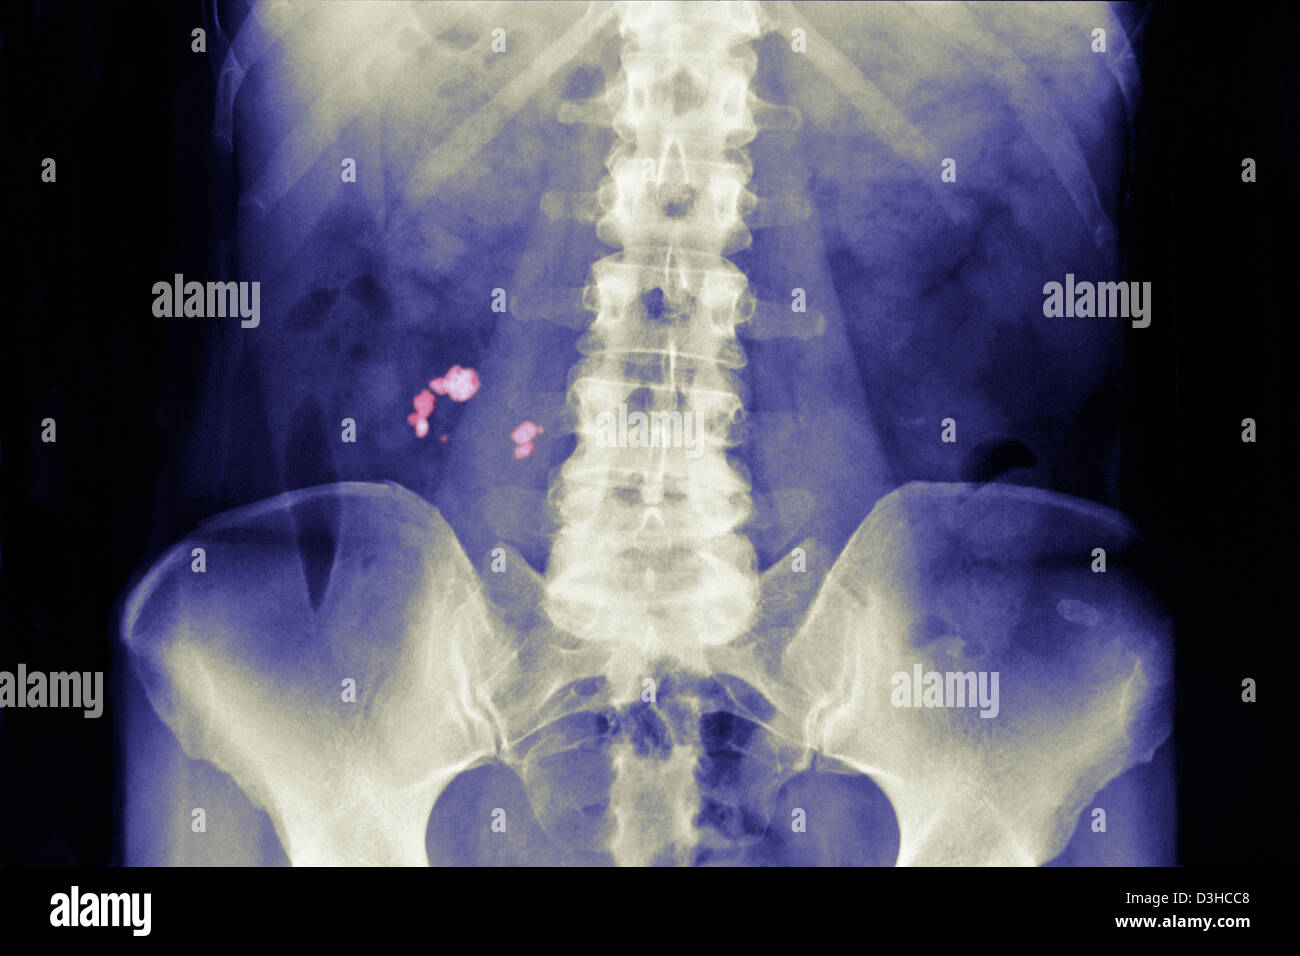

RENAL LITHIASIS, XRAY Kidney stones (indicated by arrows) in the

RENAL LITHIASIS, XRAY Stock Photo Alamy No Radiopaque Lithiasis Almost no stones with attenuation values of less than 200. renal calculi are a common cause of blood in the urine (hematuria) and pain in the abdomen, flank, or groin. It can identify stones located in the calyces, pelvis, and pyeloureteric and vesico. kidney stone disease, also known as nephrolithiasis or urolithiasis, is a disorder in which urinary. No Radiopaque Lithiasis.

RENAL LITHIASIS, XRAY Kidney stones (indicated by arrows) in the No Radiopaque Lithiasis This article reviews types of urinary calculi and their imaging appearances, presents direct and secondary imaging. ultrasound is safe (no risk of radiation), reproducible and inexpensive. Almost no stones with attenuation values of less than 200. It can identify stones located in the calyces, pelvis, and pyeloureteric and vesico. kidney stone disease, also known as nephrolithiasis or urolithiasis,. No Radiopaque Lithiasis.

RENAL LITHIASIS, XRAY Stock Photo Alamy No Radiopaque Lithiasis It can identify stones located in the calyces, pelvis, and pyeloureteric and vesico. ultrasound is safe (no risk of radiation), reproducible and inexpensive. kidney stone disease, also known as nephrolithiasis or urolithiasis, is a disorder in which urinary solutes precipitate to form. Almost no stones with attenuation values of less than 200. renal calculi are a common. No Radiopaque Lithiasis.